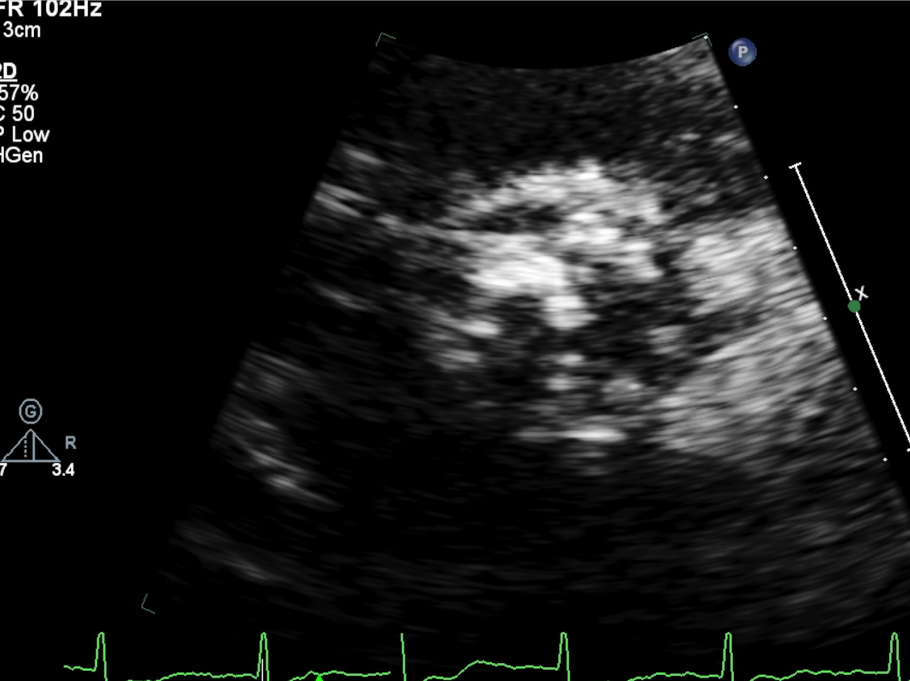

左冠风险评估

瓣膜内22mm球囊后扩张,左冠无显影